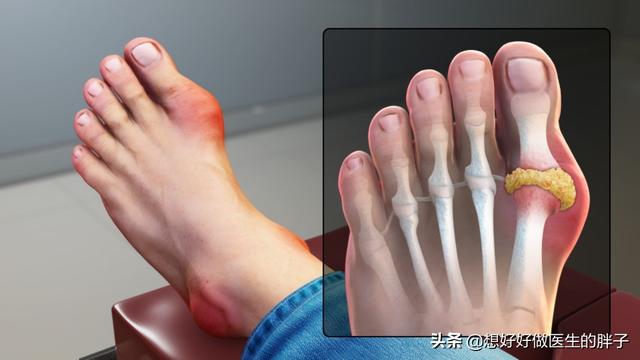

痛風この病気は、私たちの身体のプリン体代謝異常が生じ、尿酸が異常に上昇し、長期的に尿酸が上昇する。過飽和を形成することになる。尿酸塩の結晶。この尿酸塩結晶が体内に沈着し、徐々に増えていくことで、痛風の発作を引き起こす可能性がある。

而痛風発作は結晶性炎症反応の一部である痛風の発作が起きると、尿酸塩の結晶があちこちを汚してしまう。白血球しかし、尿酸塩の結晶は、特に鋭く、ちょうどその部分にある。白血球がそれを破壊しているのだ。攻撃部位に多くの炎症因子が放出されるため、患者は以下のような症状を示す。特に激しい、再燃部位の痛みそして、ローカライゼーションは迅速である。肿胀上へ。皮膚温が上昇する。また、患者によっては発症することもある。体温の異常。

痛風かどうかを判断する方法は、主に関節による。53%から70%の患者の発症当初は、第一趾の関節(足痛風と呼ばれる)が赤く腫れ、熱く痛み、通常は多発し、一部は複数の関節として現れることもある。固定性、非対称性で、次第に足首、膝、手首、肘などの大きな関節に浸潤することもある。

最初の症状は関節痛で、主に足、特に外反母趾に現れることが多い!

なぜ外反母趾なのか?理由は簡単だ。 自分の体のリンクを手に入れようとすればいい。この関節部分は比較的温度が低いことがわかるだろう。物理を学んだことがある人や溶解度について知っている人なら、温度が高いほど溶解度が大きく、逆に温度が低いほど溶解度が小さいことを知っているだろう!私たちが普段、砂糖と塩を水に溶かすように、砂糖と塩を水に溶かすのは温度が高い方が簡単だろうか?そして、温度が低いほど溶けにくいのではなく、沈殿しやすいのだろうか?この外反母趾の関節は、温度が低ければ低いほど、尿酸塩の結晶が形成されやすくなり、組織の損傷や炎症性の痛みを引き起こす!

また、これは外反母趾の関節は、外傷に対して最も脆弱な関節でもある。また、ちょっとした外傷が関節周辺のpHを変化させ、尿酸結晶の沈着を助長することもある。もちろん、痛風による関節痛はここに限ったことではなく、足背、足首、膝などが一般的な部位であり、通常は左右対称性はなく、足を触ると発赤、腫脹、熱感があり、さらに触ると熱い。

足指は尿酸塩がたまりやすい部位で、痛風に襲われると、文字通り耐え難い痛みが走る。

痛風の急性発作では、しばしば罹患した関節(最も一般的なのは母趾と足背)に著しい局所の発赤、腫脹、熱感、疼痛、機能障害がみられる。